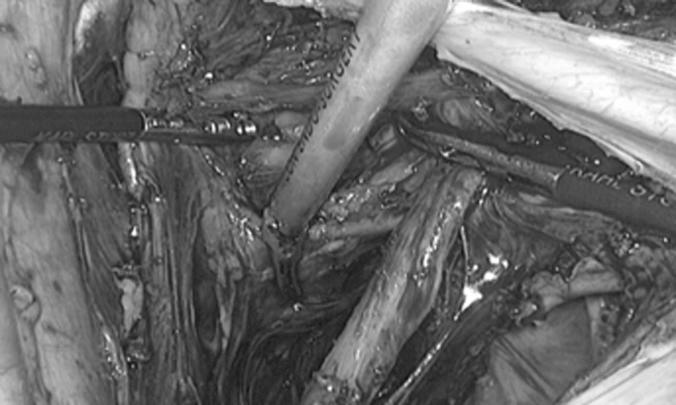

We analyzed 4 patients who underwent laparoscopic radical trachelectomy for early-stage cervical cancer between December 2011 and May 2013.

Four patients were included in this study. Total laparoscopic radical trachelectomy was performed in all cases. The mean age was 26 years (range, 19-32 years), the mean body mass index was 21 (range, 18-23), and the mean length of hospital stay was 33 hours (range, 24-36 hours). The mean operative time was 225 minutes (range, 210-240 minutes), and no complications were reported. During the postoperative period, only 1 patient presented with left vulvar edema, which resolved spontaneously. The pelvic and parametrial lymph nodes, as well as the vaginal cuff and cervical resection margins, were negative for malignancy in all cases. On average, 18 pelvic lymph nodes (range, 15-20) were removed. The tumor stage was IB in all 4 patients, and the mean tumor size was 17 mm (range, 12-31 mm). No patient required conversion to laparotomy.